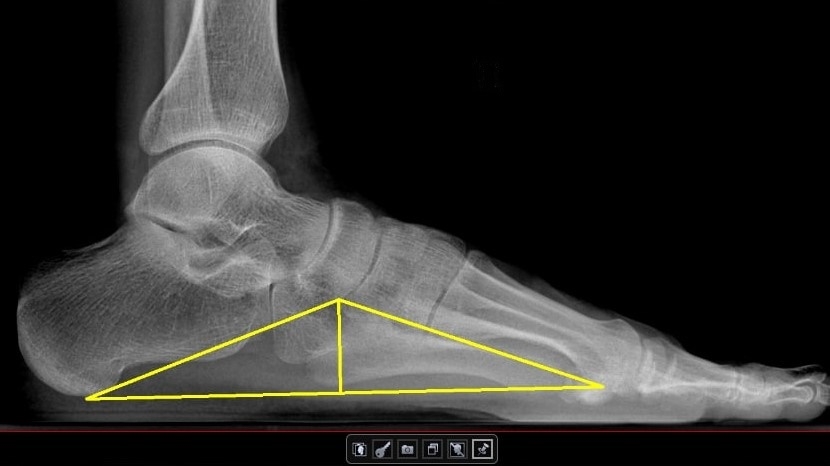

«Рентгенологи Москвы теперь могут воспользоваться искусственным интеллектом для распознавания признаков плоскостопия. Нововведение упрощает и ускоряет диагностику заболевания, а также определение его степени, позволяет врачам экономить время на описании нормы и результатов исследований. Благодаря расширению возможностей цифровых сервисов, сейчас умные алгоритмы помогают в поиске заболеваний уже по одиннадцати различным направлениям. Отмечу, что новый сервис для распознавания плоскостопия на рентгенографии – это отечественный продукт», – рассказал Илья Тыров.

Прежде чем допустить искусственный интеллект к анализу снимков лучевых исследований пациентов городских медицинских учреждений, научные сотрудники, инженеры и врачи-эксперты тестируют сервисы искусственного интеллекта. Новый сервис успешно прошел функциональные и калибровочные испытания, отмечает директор Центра диагностики и телемедицины ДЗМ Юрий Васильев: